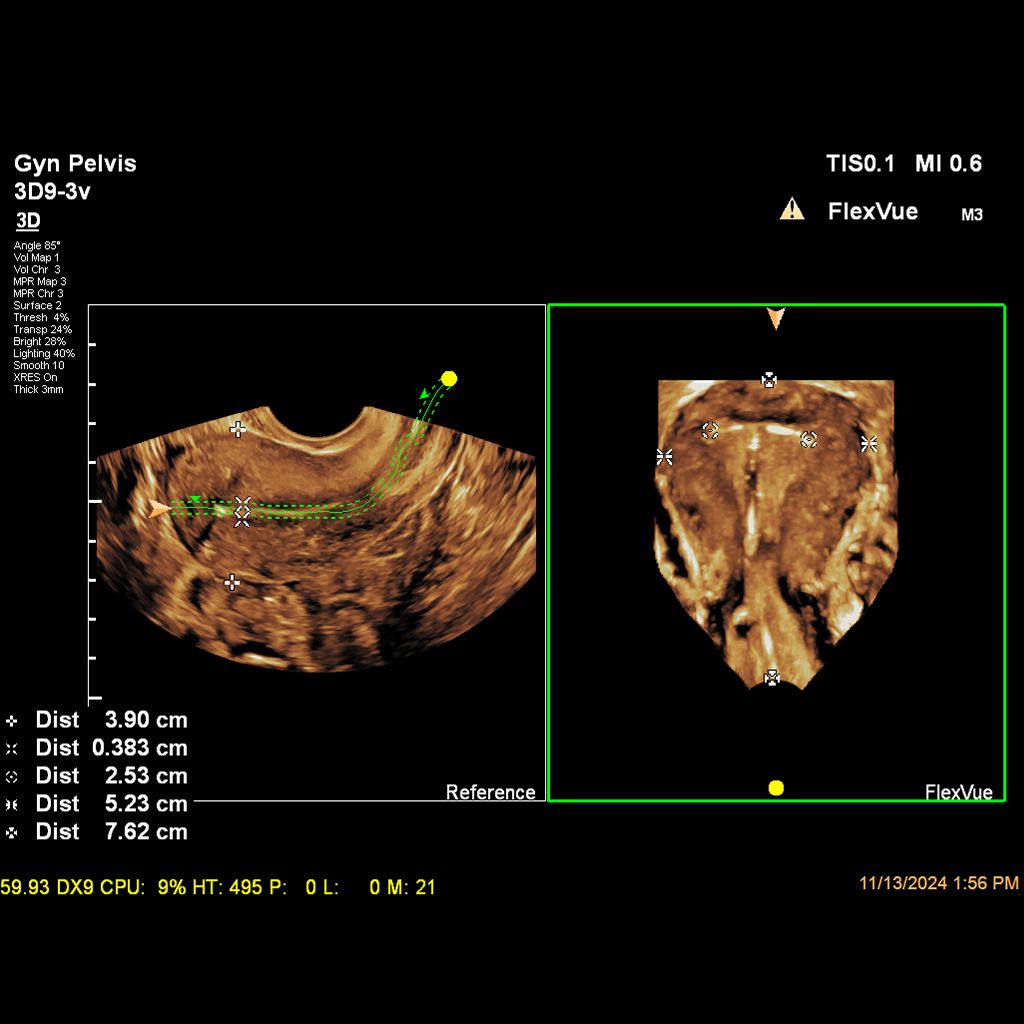

Demonstrated results using FlexVue

It (FlexVue) takes all of the complications out of MPR and manipulation of a surface-rendered volume. By deploying a straight line or a curved trace or continuous trace, we can take a curved image, flatten it out and make it a single planar image.